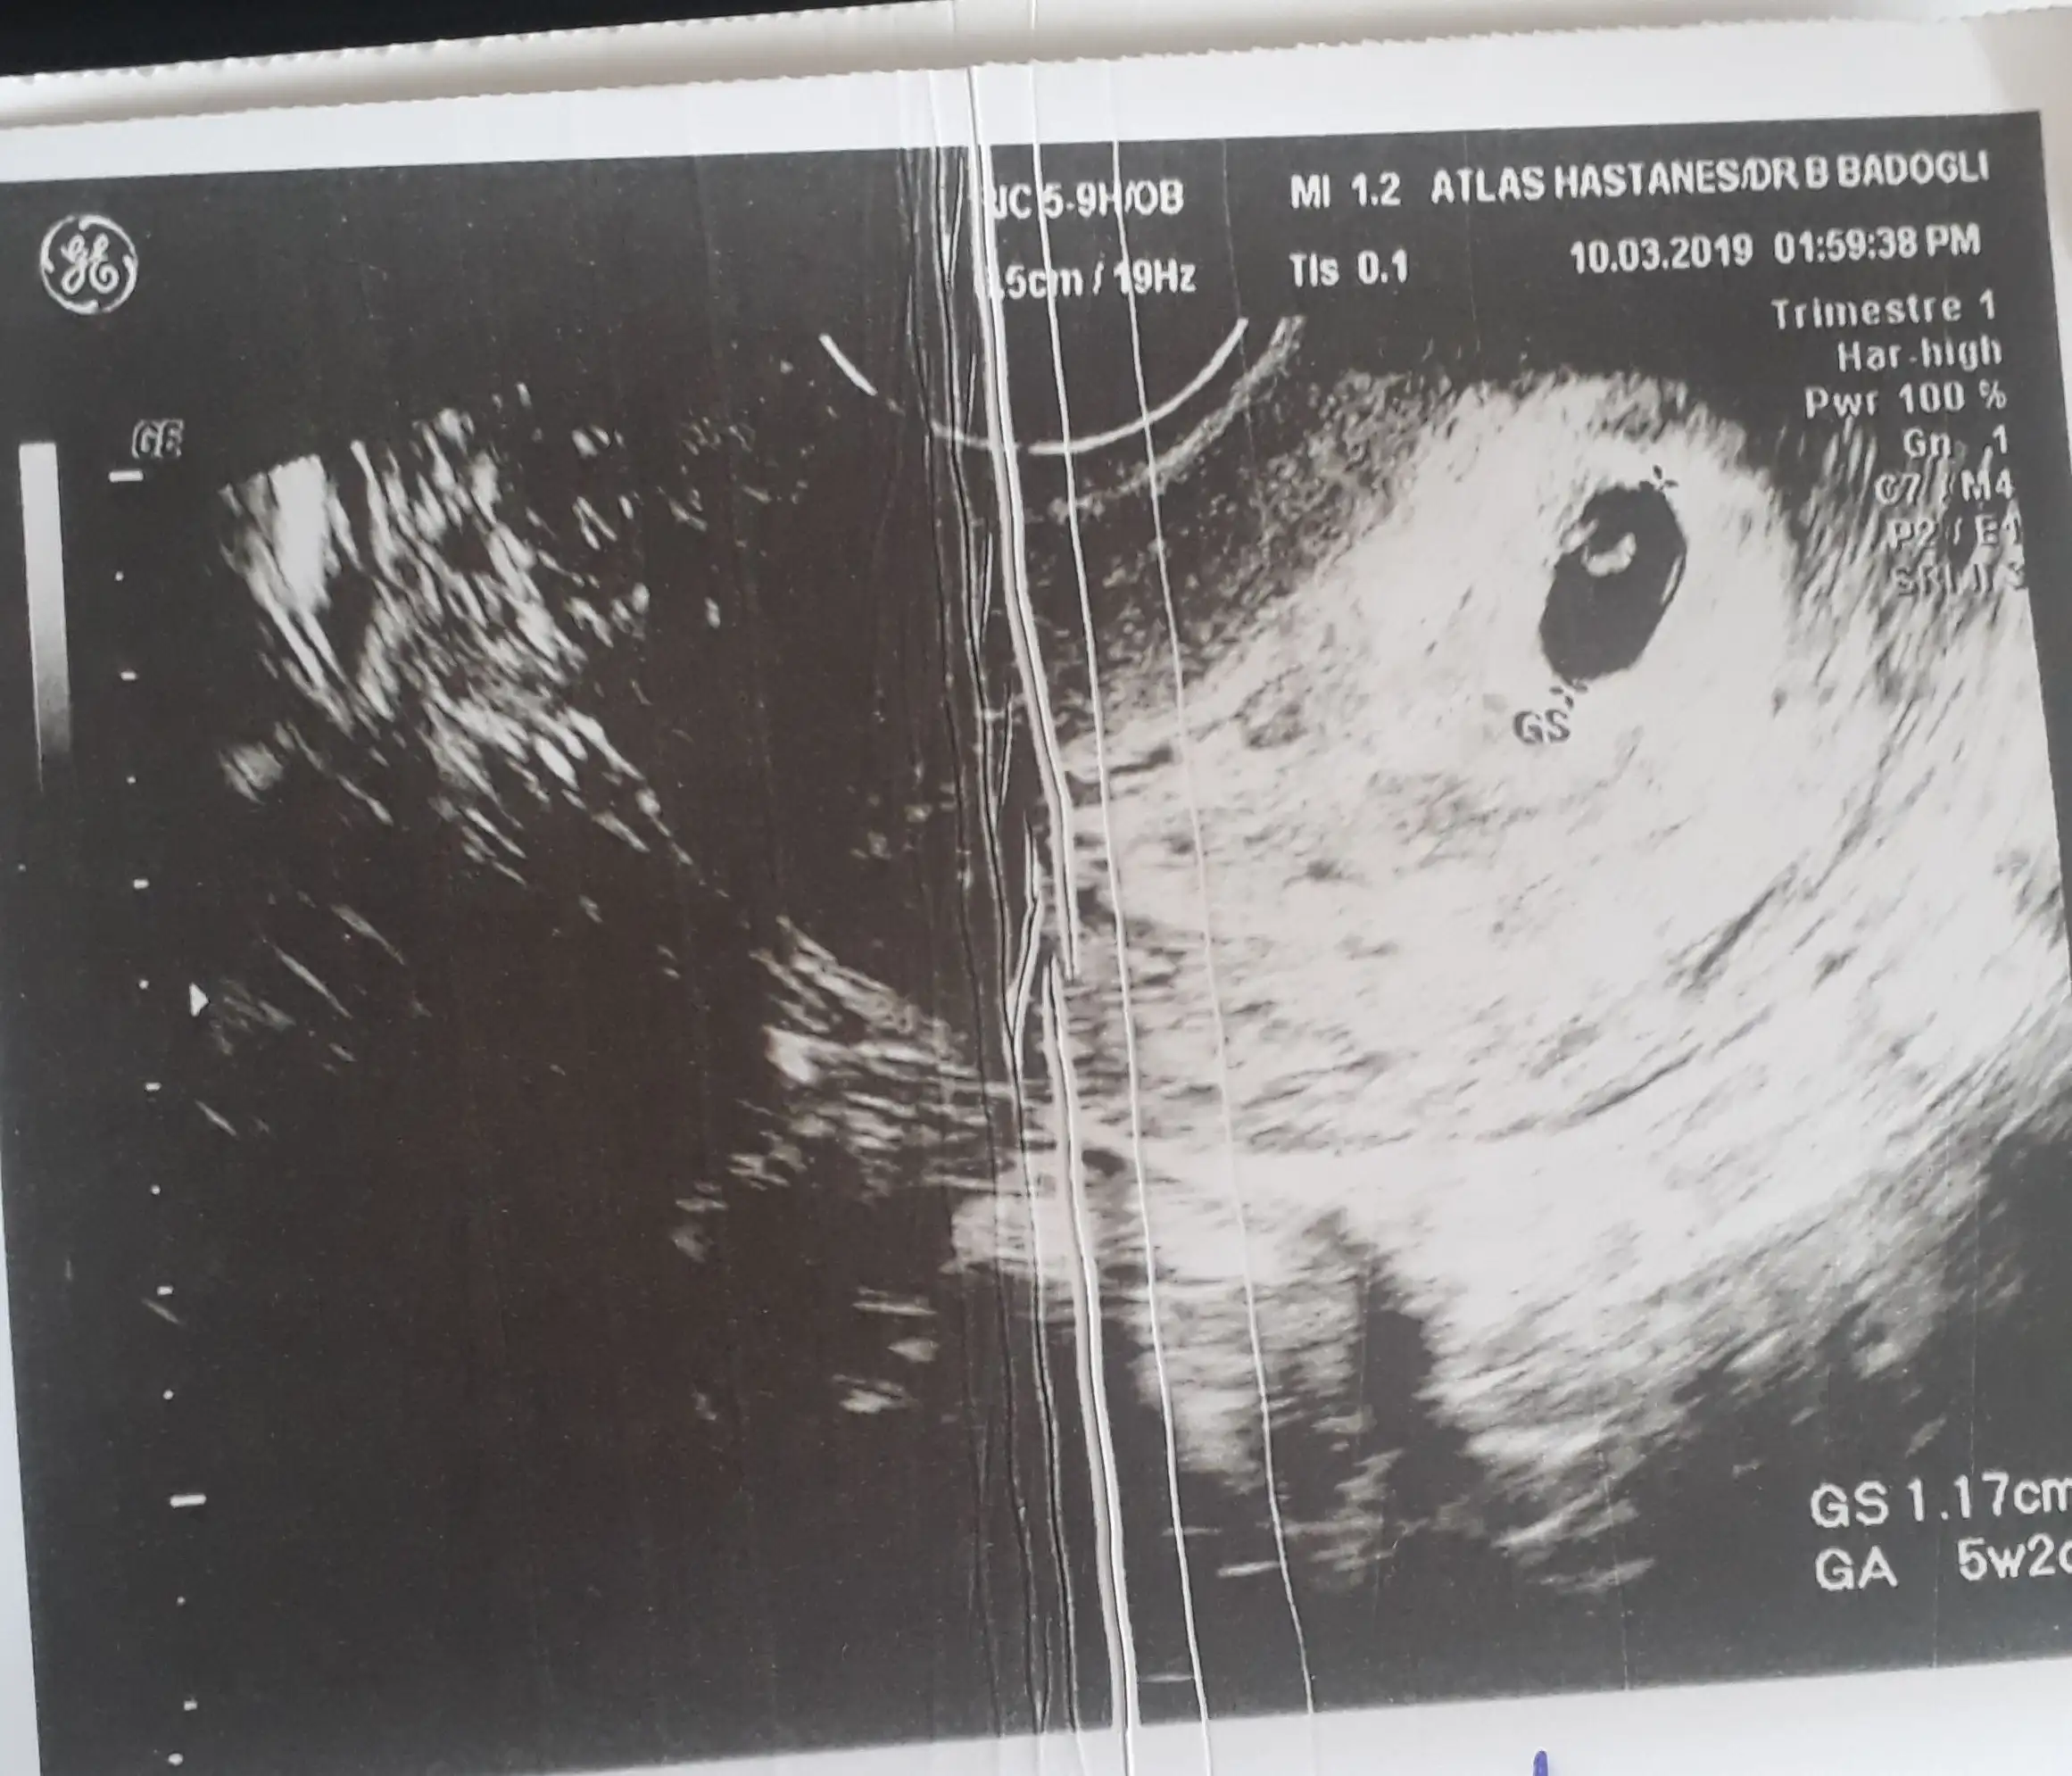

Kese en erken bhcg 1500-2000 ulaşınca görülüyor. 133de görünmemesi gayet normal. Anormal bir durum değil yani korkma

İnş görücez bi de kalp atışı da görülse sürpriz olurdu ne güzel

Sat ımız aynı. Bhcg değerine göre değişir gözüküp gözükmeyeceği tabi ama sabredemem diyosan görücem diye şartlams kendini bi de doktor göremedim falan derse de hemen korkma. Bazı doktorlar açıklama yapmadan görmedim sonra tekrar bakalım deyince insan pimpirikleniyor.